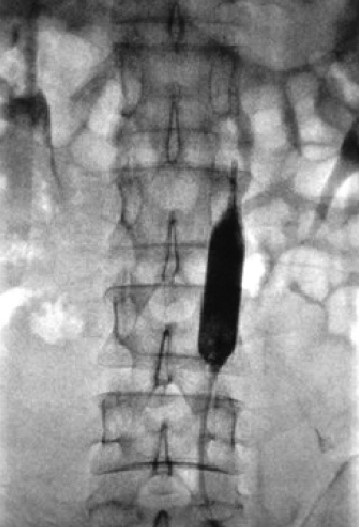

三、骨盆血供丰富,手术出血多,如何减少术中出血?

3.供瘤血管介入栓塞